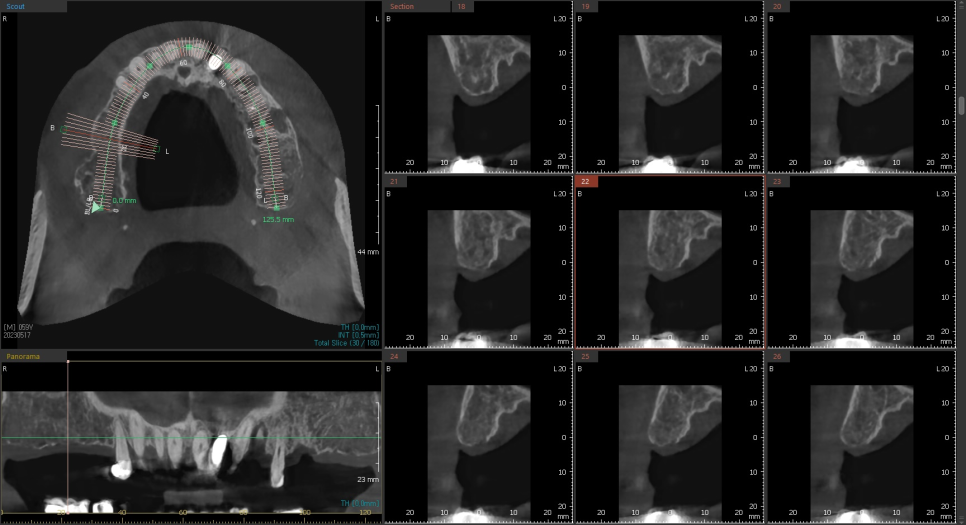

최근 즉시로딩 케이스를 하나 소개드리자면

작은 어금니쪽은 뼈가 살짝 얇지만, 큰 어금니로 갈수록

가용할수있는 잔존골이 많은것을 확인할수 있습니다.

하지만 아래턱에 비해서 골질이 약할수밖에 없는 위턱에 심는 임플란트이고

잔존골의 폭경 또한 만족할만큼 넓진않았기때문에

임플란트 주위로 최소 1mm를 확보하기위해

직경이 얇은 임플란트와와 네비게이션 수술을 선택하였습니다.